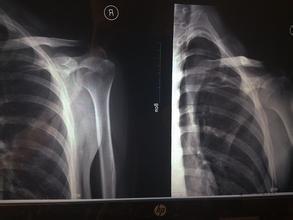

肩胛骨体部骨折多为强大的直接暴力或火器伤引起。如重物或火器伤直接损伤肩胛骨体部,多为粉碎性骨折,有时亦有横行或斜行骨折,因肩胛骨前后均有肌肉保护,多无明显骨折移位,但须注意有无肋骨骨折或胸腔脏器伤。